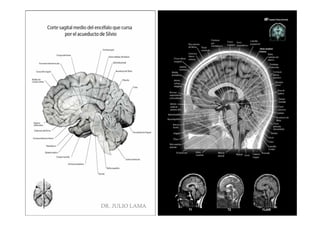

DR. JULIO LAMA

Pregrado – Dr Yee